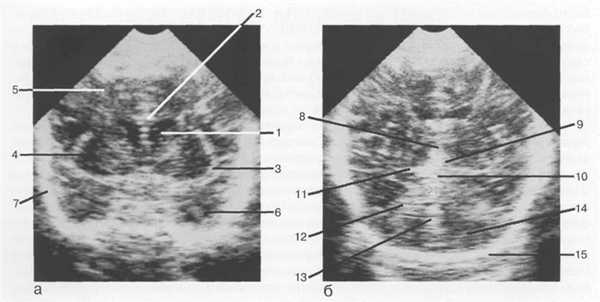

Рис. 1.1. Нейросонография. Изображения головного мозга в сагиттальной плоскости: а — срединно-сагиттальный срез; б — парасагиттальный срез через тела боковых желудочков.

I — поясная борозда; 2 — мозолистое тело; 3 — межжелудочковое отверстие; 4 — сосудистое сплетение нижнего рога; 5 — клубок сосудистого сплетения; 6 — III желудочек; 7 — височная доля; 8 — лобная доля; 9 — теменная доля; 10 — инфундибулярный карман; 11 — водопровод среднего мозга; 12 — четверохол-мная цистерна; 13 — IV желудочек; 14 — мозжечок; 15 — межталамическая спайка.

Рис. 1.2. Нейросонография. Изображения головного мозга в корональной плоскости: а — через передние рога боковых желудочков; б — через структуры задней черепной ямки.

1 — передний рог бокового желудочка; 2 — мозолистое тело; 3 — латеральная щель мозга; 4 — островок; 5 — лобная доля; 6 — височная доля; 7 — чешуя височной кости; 8 — III желудочек; 9 — цистерна промежуточного паруса; 10 — четверохолмная цистерна; 11 — охватывающая цистерна; 12 — намет мозжечка; 13 — червь мозжечка; 14 — полушария мозжечка; 15 — затылочная кость.